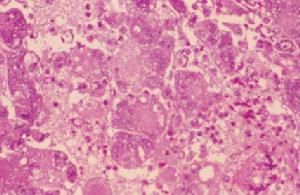

白喉的傳染源是白喉病人及恢復期帶菌者。該菌存在於假膜及鼻咽腔或鼻分泌物內,經飛沫、污染物品或飲食而傳播。白喉桿菌侵入易感者上呼吸道,通常在咽部黏膜生長繁殖,並分泌外毒素及侵襲性物質,引起局部炎症和全身中毒症狀。局部黏膜上皮細胞發生壞死,血管擴張,粒細胞浸潤及纖維滲出,因此形成灰白色膜狀物,稱為假膜(Pseudomembrane),若病損進一步擴展至喉部或氣管內,可引起呼吸道阻塞,甚至窒息。儘管細菌一般不侵入血流,但外毒素可被吸收入血,迅速與易感組織細胞結合,使心肌、肝、腎和腎上腺等發生退行性病變,並可侵犯齶肌和咽肌的周圍神經細胞,臨床上出現心肌炎和軟齶麻痹、聲嘶、腎上腺機能障礙,血壓下降等症狀。該菌偶有侵害眼結膜、外耳道、陰道和皮膚傷口等處,也可形成假膜。